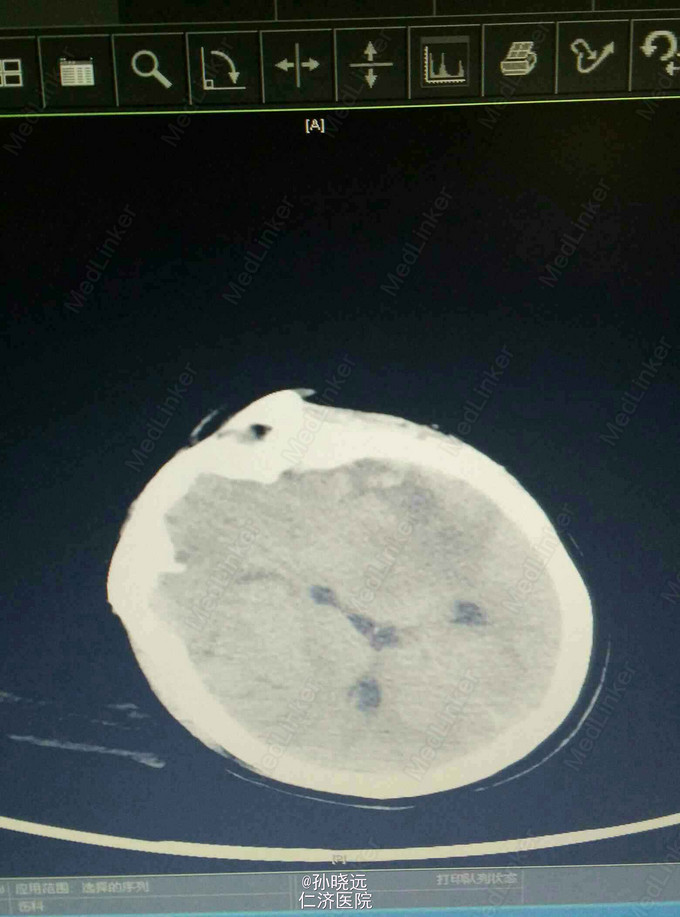

中年女性。主诉:头晕三天,发热伴神志不清1天。 患者于三天前出现持续性头晕,无恶心、呕吐,无视物旋转,来院就诊,查头颅MRI未见异常,予桂哌齐特、长春西汀、硫辛酸治疗,症状无好转。1天前出现高热,最高39.5℃,无咳嗽、气促,再次来院就诊,查血常规:WBC:5.85*10^9/L,N:71.8%,CRP正常,予退热,阿奇霉素等治疗,今日凌晨出现神志不清,无抽搐、恶心、呕吐,头颅CT示两侧颞底部不规则斑点样密度增高影并周围低密度灶,考虑脑炎合并灶性出血,予更昔洛韦、醒脑静、喜炎平、奥美拉唑、甘露醇治疗。后出现氧饱和度下降,予气管插管有创呼吸机辅助通气。 既往史:曾有高血压病史,未应用降压药。

诊断:脑炎。脑出血。 治疗:甲强龙抗炎,更昔洛韦,青霉素钠抗感染,降压,甘露醇、甘油果糖、白蛋白、拖拉塞米里降颅压,呼吸机辅助通气等对症治疗。

腰穿是: 脑脊液生化:葡萄糖:12.18mmol/L,CL:110.9mmol/L,蛋白:222.4mg/dl, 脑脊液常规:淡黄,微混。红细胞:1000*10^6/L,白细胞:1059*10^6/L,潘氏试验阳性(++++),嗜中性粒细胞12%,淋巴细胞:80%,单核细胞8%,凝块无,细菌未找到。 予加用血必净,加强抗感染等治疗。 患者目前仍昏迷,正进行高压氧仓治疗。这是最近一次复查的头颅CT。